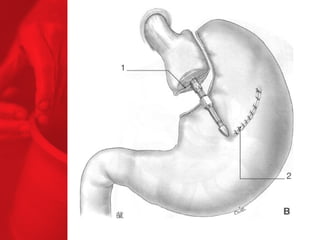

GASTRIC BYPASS Lesprocédures de malabsorption et restrictives > 56% de perte de poids excédentaire après quatre ans* > diminue le diabète de type 2 chez plus de 83 % des patients* *Christou NV, Sampalis JS, Liberman M, et al. Surgery Decreases Long-Term Mortality, Morbidity, and Health Care Use in Morbidly Obese Patients. Annals of Surgery 2004;240(3):416-424. ** Buchwald H, Avidor Y, Braunwald E, et al. Bariatric Surgery—A Systematic Review of the Literature and Meta-analysis. Journal of the American Medical Association 2004 Oct 13;292(14).

COMMENT FONCTIONNE LECOURT-CIRCUIT GASTRIQUE ? Facteurs chirurgicaux Restriction du volume des repas Certaine malabsorption Syndrome de chasse Réduction de l'appétit Facteurs pour les patients Apport en calories Dépense en calories BILAN ENERGETIQUE = apport alimentaire dépense en énergie

Points importants •  La GVC est plutôt indiquée pour l'adulte hyperphage, sans trouble majeur du comportement alimentaire, même s'il existe une hernie hiatale avec un RGO non sévère, II peut être fait un geste antireflux. Ce geste est proposé aussi aux patients refusant un anneau modulable implantable (et boîtier d'ajustage). •  Le CCG ou bypass gastrique (court-circuit gastrojéjunal) est proposé à l'adulte « superobèse » (IMC > 50 kg/m2), ayant des troubles du comportement alimentaire (compulsif), une hernie hiatale avec un RGO, associée à une œsophagite très sévère. II est proposé en seconde intention en cas d'échec des interventions de restriction gastrique.  •  La technique de gastrectomie pariétale en gouttière avec diversion biliopancréatique est à réserver aux « superobèses » (IMC > 60 kg/m2) et au syndrome de Prader-Willi. •  La gastrectomie longitudinale en manchette, le cerclage gastrique modulable au la gastroplastie verticale bandée peuvent faire maigrir les « superobèses » avant de leur proposer une chirurgie de malabsorption en seconde intention et avec un moindre risque chirurgical sous laparoscopie.